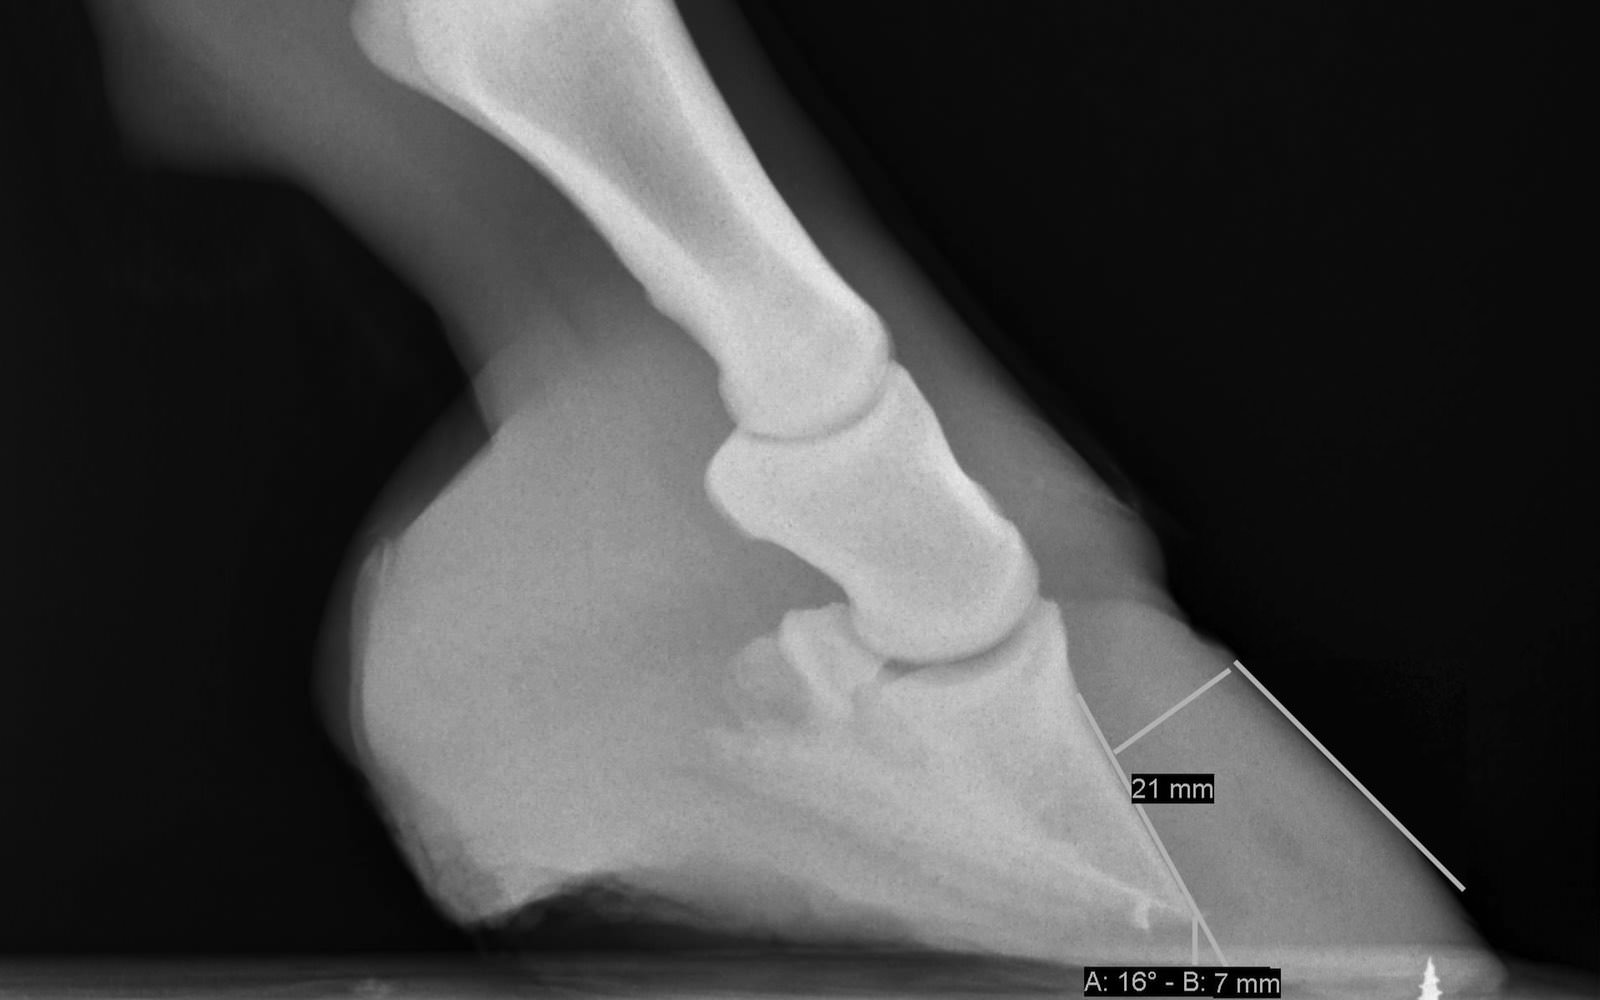

• Digitales Röntgen